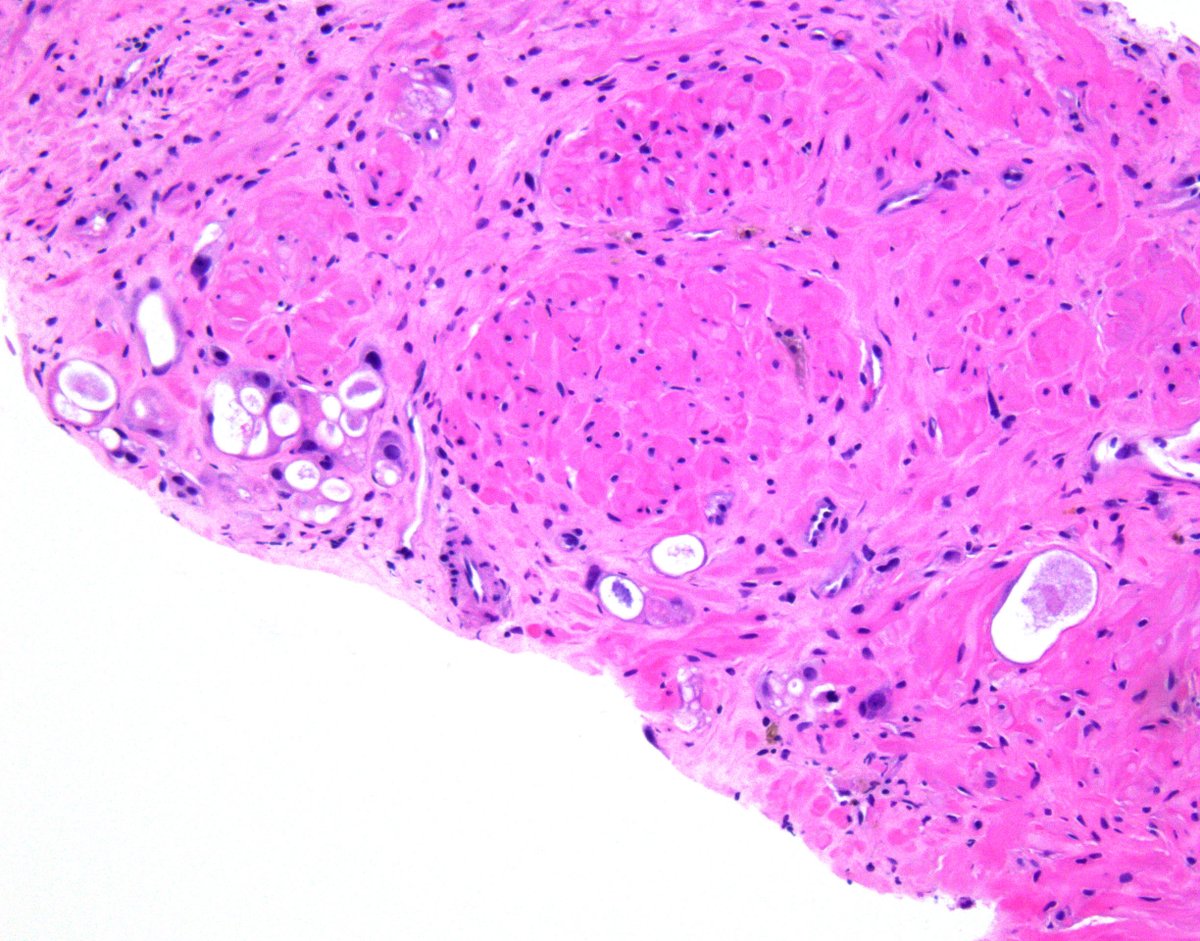

Textbook images of prostate NB with therapy-related changes #gupath ☢️ Poorly-formed glands/single cells w/vacuolization & prominent nucleoli = #ProstateCancer ☢️ Multi-layered glands w/eosinophilic cytoplasm, variable nuclear size & fine peri-glandular fibrosis = Benign